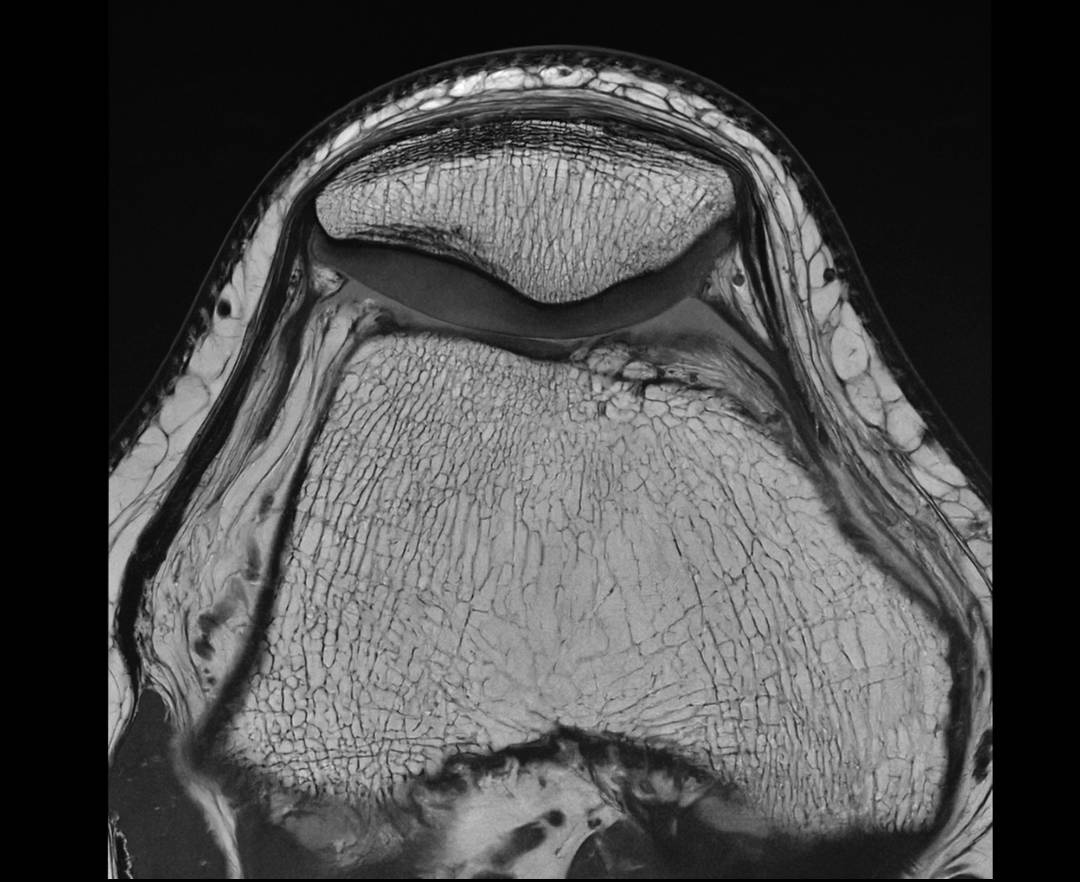

KNEE PD SAG

KNEE PD TRA